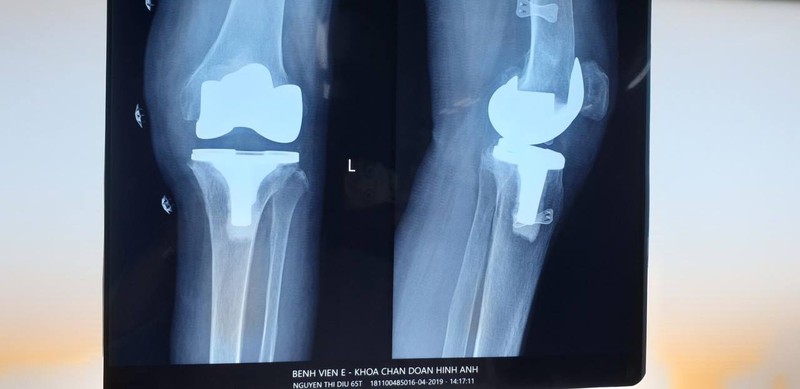

Ảnh chụp Xquang khớp gối của bệnh nhân

“Chân bệnh nhân co rút, gấp hơn 30 độ nên rất khó phẫu thuật. Bên cạnh đó, các triệu chứng thoái hóa khớp gối cho thấy bệnh nhân đã bị tổn thương sụn khớp nghiêm trọng. Khớp sưng đau cản trở việc vận động của bệnh nhân, khiến có thể dần bị mất hoàn toàn chức năng vận động” – Bác sĩ Hiền cho biết.

Thể trạng bệnh nhân gầy yếu, nguy cơ biến chứng cao, tỷ lệ thành công thấp, nên việc phẫu thuật đòi hỏi bác sĩ phải thực hiện các kỹ thuật cao, thao tác chính xác.

Tuy nhiên, các bác sĩ vẫn quyết tâm phẫu thuật cho bệnh nhân. Sau 2 giờ tiến hành ca mổ, bệnh nhân được thay khớp gối toàn phẩn. Sau 1 tuần, bệnh nhân đã tập đi trở lại và có thể sớm xuất viện.